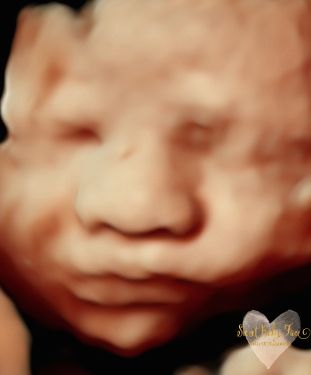

3D/4D/5D Ultrasound Gallery

Take a peek at our Photo Gallery. All of our 2D, 3D, 4D, HD elective ultrasound images are truly ours. They come directly off our machine from our highly trained staff. We can start getting great 3D/4D images as early as 10 weeks!